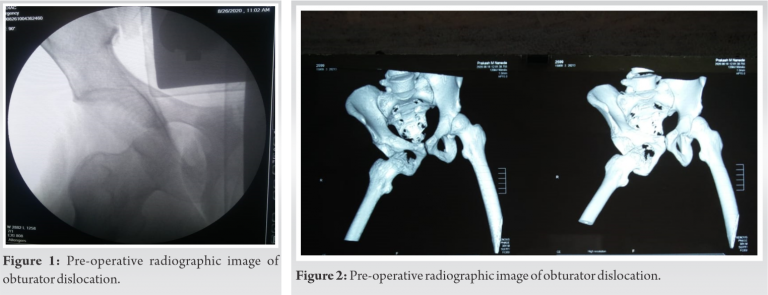

Mr. SH, A 35-year-old male patient presented to us with a history of fall from a height of 15 feet after which he was unable to bear weight on right lower limb. He was treated by a local quack in his village. He continued to experience pain for the next 6 months after which he presented to our emergency department with an antalgic gait. On clinical examination, he had a right lower limb abduction and external rotation deformity with painful restricted movements. Radiological imaging confirmed the clinical suspicion of anterior hip dislocation of obturator variety (Fig. 1, 2).